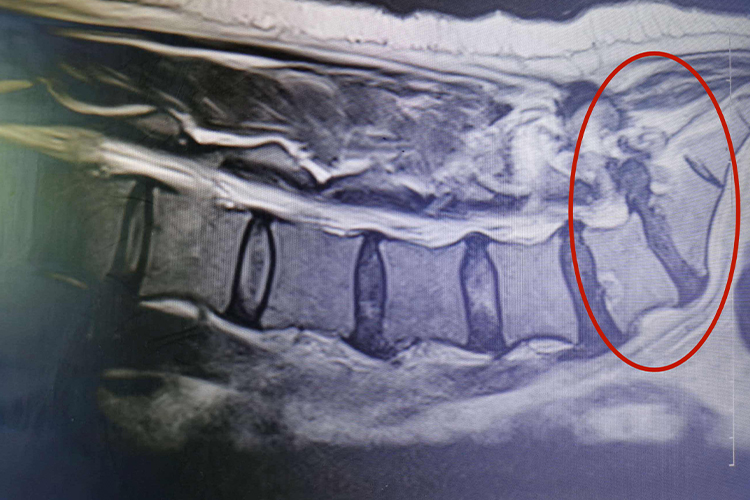

腰5骶1椎间盘突出中央型,主要是第5腰椎与第1骶椎之间的椎间盘突出,从后纵韧带处突出,可能穿破后纵韧带,位于硬膜囊的前方,主要压迫马尾神经,也可压迫单侧或双侧神经根,出现腰痛、坐骨神经痛、肌瘫痪、下腹部痛,或大腿前侧痛、间歇性跛行、麻木等症状。

出现腰5骶1椎间盘突出中央型后,建议遵医嘱绝对卧床休息,使用双氯芬酸钠缓释胶囊等消炎止痛药物治疗,可配合推拿、持续牵引、按摩、理疗等方法联合治疗。必要时可选择微创手术治疗。